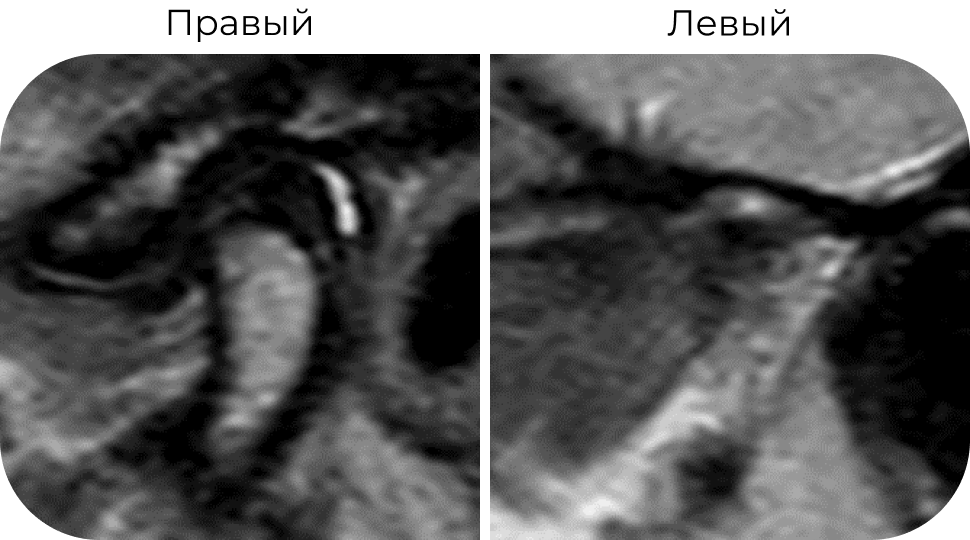

МР-картина выраженных дегенеративных дистрофических изменений левого мыщелкового отростка и деформация головки, учитывая в анамнеза травму 15 лет назад возможно травматического генеза.

Деформация с признаками застарелого повреждения промежуточной зоны, дислокация и малоподвижность суставного диска слева (признаки адгезии диска). Признаки гипомобильности ВНЧС слева.

Справа отмечается вентролатеральная дислокация суставного диска с репозицией при открывании рта.

Умеренный синовит.